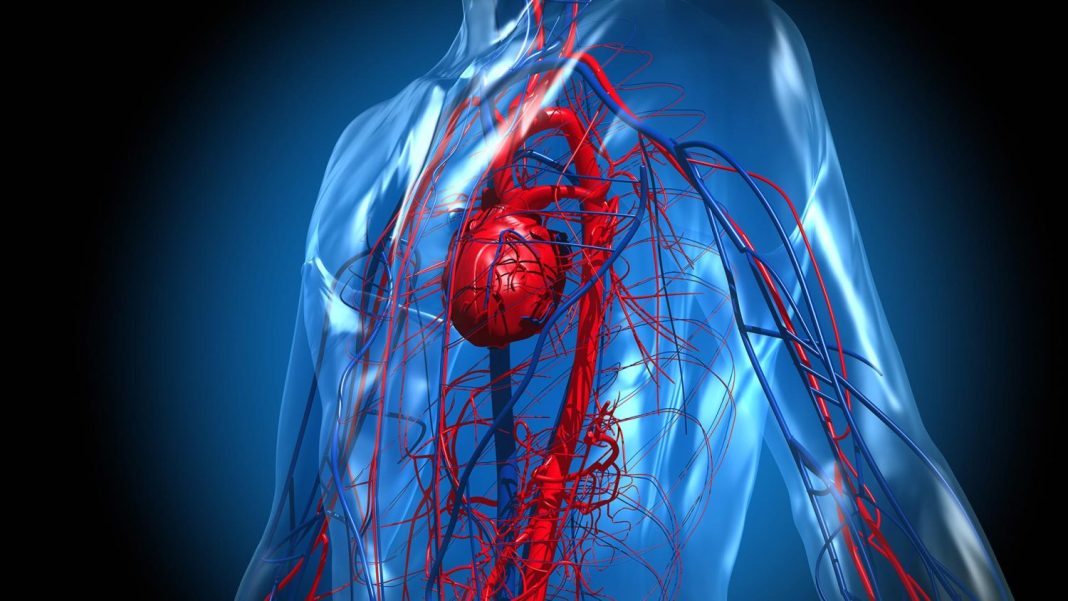

Desde febrero de 2022, la AEMPS no permite que se compre SGLT2 inhibitors en la farmacia. Sacó del mercado varios productos de esta clase. Se utilizaban para el tratamiento de la diabetes, pero se sacaron porque tenían unos efectos adversos que podían ser altamente perjudiciales para los consumidores, como problemas cardíacos, infecciones graves y cánceres genitales.